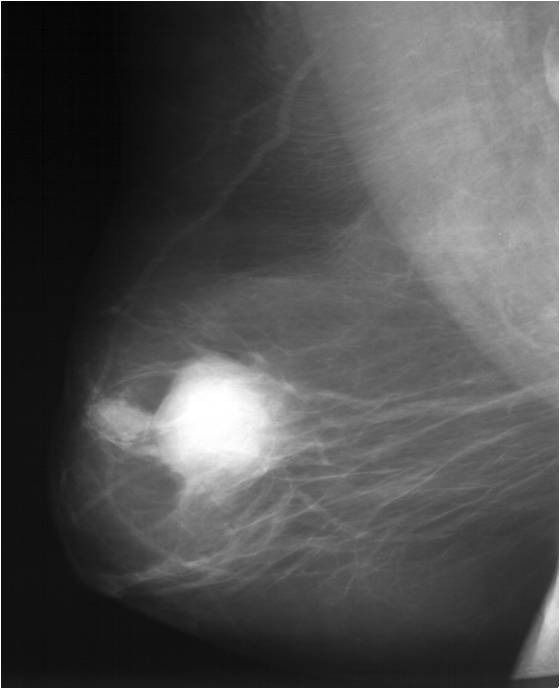

Для выявления злокачественных опухолей молочной железы существует определенный алгоритм диагностики, и его первичный элемент — маммографический скрининг. Чувствительность этого метода диагностики для опухолей от 2 мм до 5 мм составляет около 85%. Маммографическое исследование выполняют в двух проекциях.

Цифровая маммография РМЖ

Молодым женщинам с плотным строением молочной железы необходимо включение в программу наблюдения методов УЗИ и МРТ.